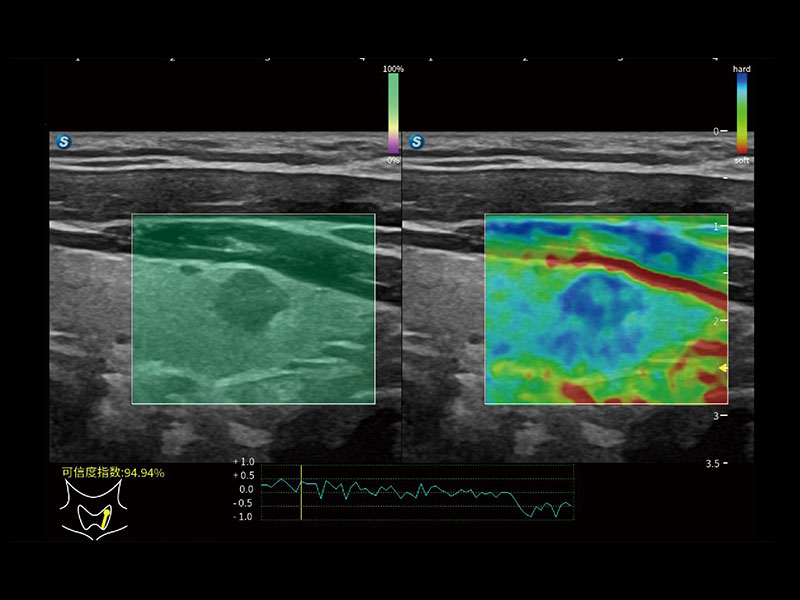

便携式彩色多普勒超声诊断系统

作为开立医疗全新打造的高端全域笔记本超声,X11集成了当前先进的硬件架构和精密的设计工艺,提升多科室临床医生在常规影像检查中的诊断能力,为临床提供全面的诊疗支持。

信噪比提升

分辨率&均一性提升